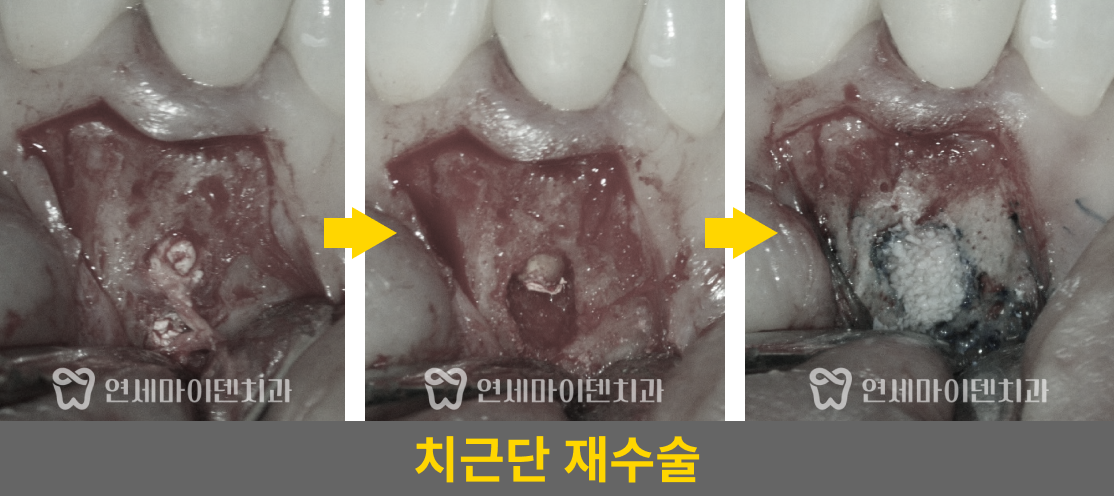

■ 환자의 주요 증상과 진단 과정

■ #25번, 첫 번째 치아 치료 - 재신경치료

치료를 조금만 하면 개선의 여지가 있겠다는 생각이 들어, 우선은 재신경치료를 하기로 했습니다.

거타퍼차 콘(GP cone)을 하나씩 꽂는 방식이 아닌, 수직 가압 충전법을 사용하여 거타퍼차 콘을 녹여 충전하는 현대적 방식으로 진행하였습니다. 레진 충전시에도 임시 재료 없이 원칙적인 치료로 진행했습니다.